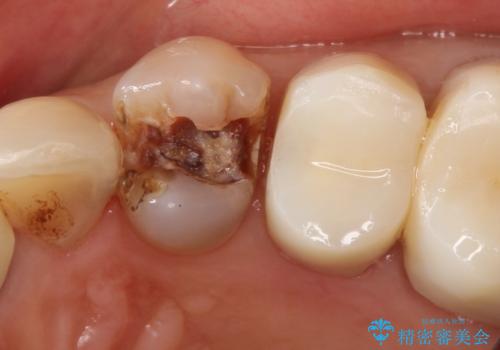

銀歯を外すとかなり大きな虫歯になっていました。幸いぎりぎりのところで神経まで虫歯は広がっていなかったため、症状が出ない事を確認した後、オールセラミッククラウンで治療しました。虫歯除去後、残っている歯質が少なかったため、破折抵抗を考慮し部分的な被せ物ではなくクラウンを選択しました。

※被せ物では歯と被せ物の適合がとても大切になります。適合が悪い被せもの(歯と被せものの間に隙間がある)を入れるとそこに汚れが溜り虫歯の原因となります。当院では精度が高い被せものを追求するため、サージテル(拡大鏡)や型取りの材料にシリコン材を使用しています。